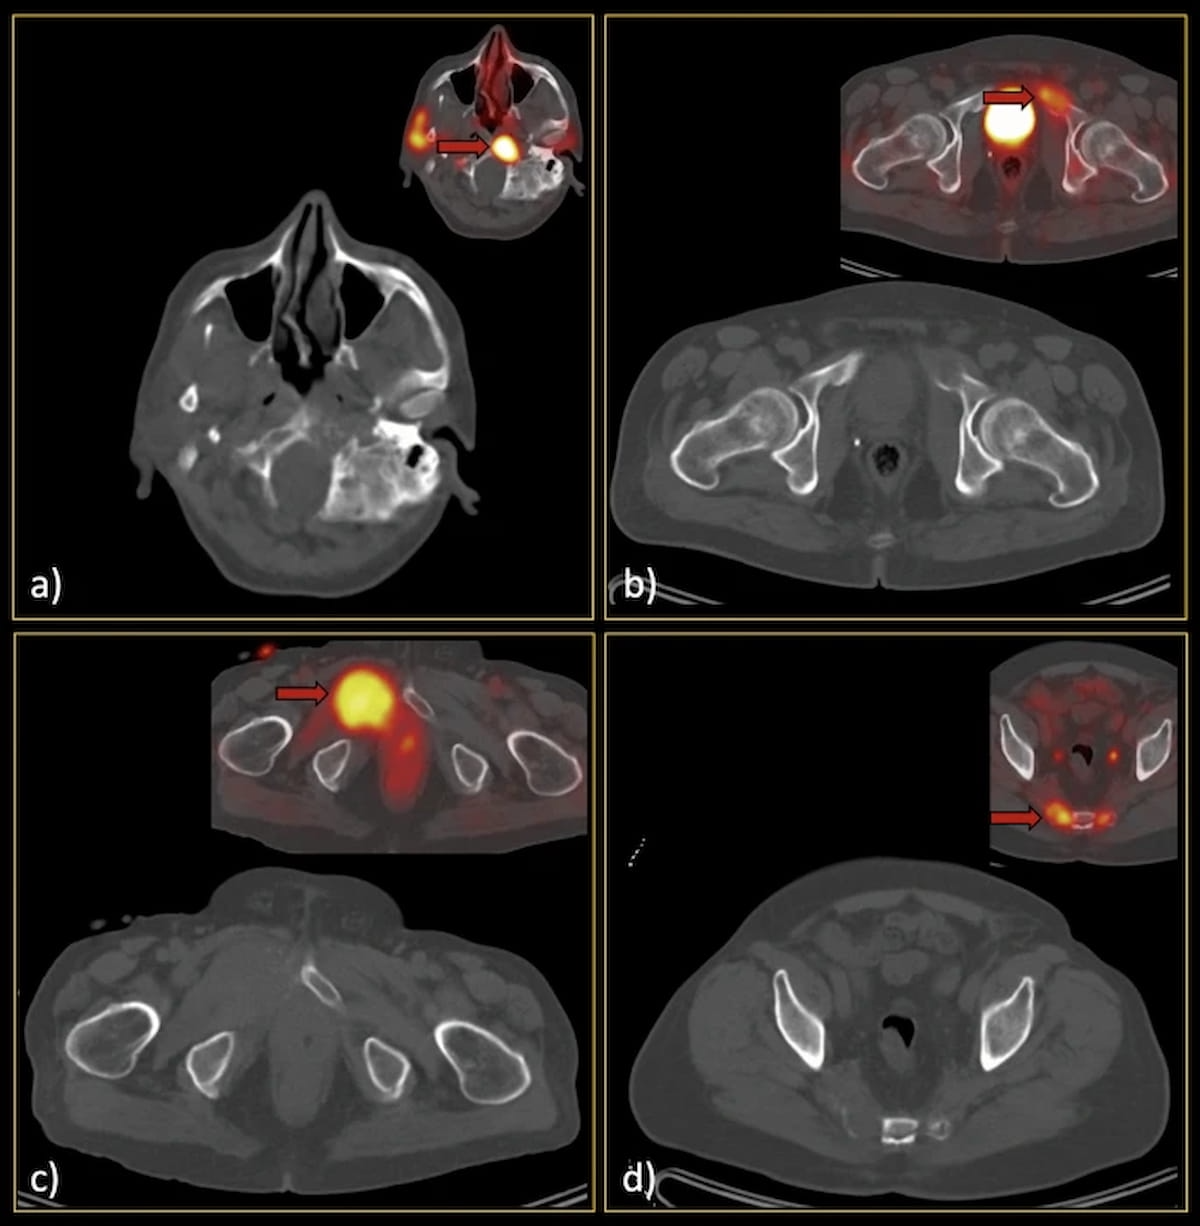

Examining the use of the Response Evaluation Criteria in Prostate-specific Membrane Antigen (PSMA) PET/CT (RECIP 1.0) model for assessing the treatment of metastatic castration-resistant prostate cancer, researchers found robust agreement between quantitative application of RECIP via tumor segmentation software and qualitative application of the model through reads by nuclear medicine physicians.